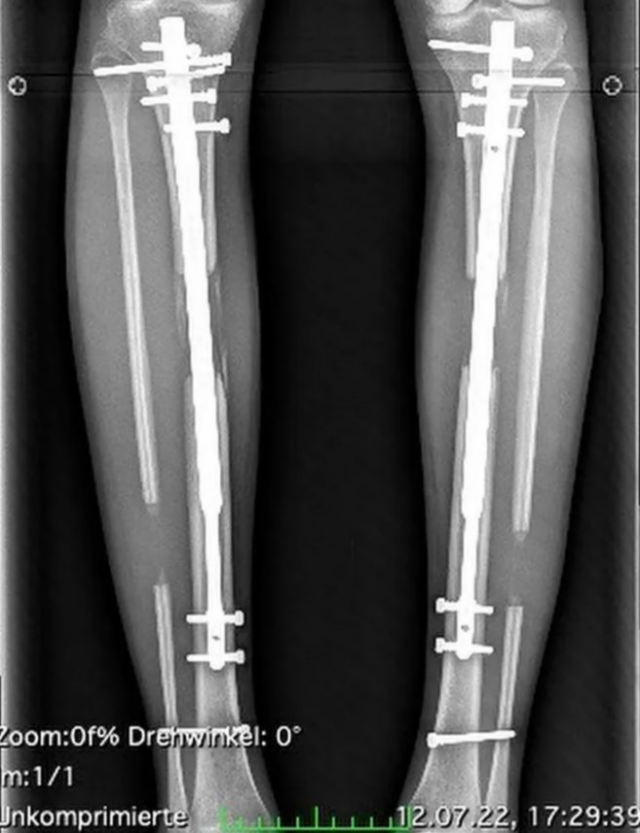

Milli.Az xarici mətbuata istinadla bildirir ki, realiti şou ulduzu Theresia Fischer keçmiş sevgilisi Thomas Behrendin istəyi ilə 167 min dollar xərcləyərk boyunu uzadıb.

2016-cı ildə əməliyyata başlayan modelin boyu 14 sm uzadılıb. Belə ki, 2022-ci ildə artıq qızın boyu 170-dən 184-ə qalxıb.

Hər əməliyyatda ayaq sümükləri uzadılan qızın ayağındakı metallar ötən ay çıxarılıb.